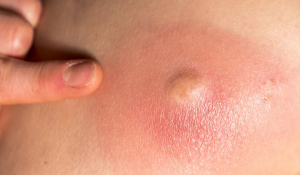

Гнійні захворювання шкіри: причини виникнення та методи лікування

Зазвичай пацієнти вважають, що гнійні захворювання шкіри є малозначними, тому дуже часто борються з ними самостійно, народними методами, а це дуже неправильно. Адже ці захворювання можуть призвести до поганих наслідків.